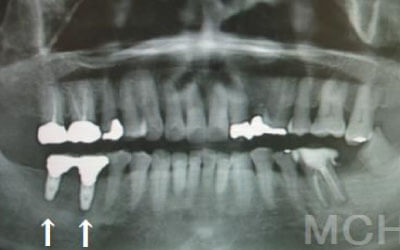

特に、抜けたのが前歯ですとなおさら気になりますよね。 今回のご質問ですが、抜けた部分の骨が薄いなどの理由で「インプラントはできない」と言われた可能性があります。

前歯はもともと骨が薄く、歯が抜けると時間の経過とともにさらに骨が痩せてきてしまうので、インプラント治療の難易度が高い場所です。 ただ結論からお話すると、インプラント治療は可能です。

なぜなら、もし仮に骨が薄くても、骨の治療によって厚みが増せば、安全にインプラント治療が行えるからです。

なお、前歯のインプラント治療をご希望の方には、注意していただきたい点が4つほどあります。 1)インプラント治療を行う前に、骨の治療が必要かもしれません。

2)骨の治療から始めると、その分、治療期間が長くなります。

3)骨の治療は、通常のインプラント治療よりも難易度が高いため、経験の豊富な先生やインプラント認定医のいる歯科医院で治療を受けることをお勧めします。

4)骨の状況をしっかり把握するためにも、CT撮影が必須となります。 また、インプラント治療においては、周囲の歯の状況や咬み合わせの問題などもしっかりと考えて治療するのがとても大切です。